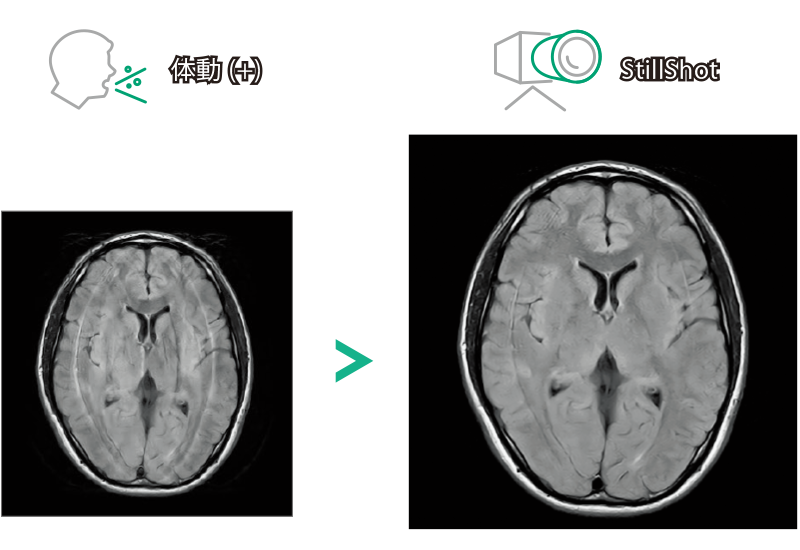

FLAIR

T1WI Dual Echo (Out) 息止め

T2*WI RADAR, 2:34

T2WI FatSat 呼吸同期併用RADAR, 2:16